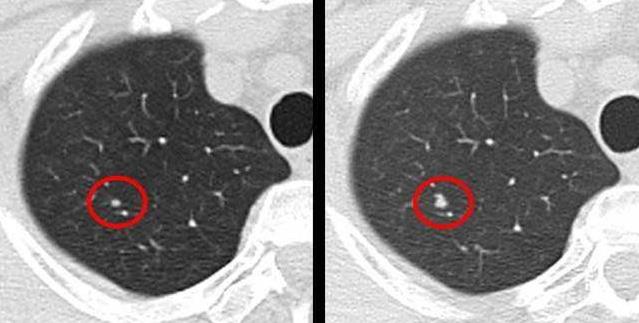

随着人们健康意识的提高,对肺癌早查早治的认识。胸部CT检查逐渐在中国得以广泛的开展,也因此越来越多人在检查中,被发现有为症状的“肺部小结节”。发现的直径在10 毫米左右的结节病变。在临床中,一般把小于7毫米的结节叫做微小结节,而3毫米以下的结节叫做微结节。